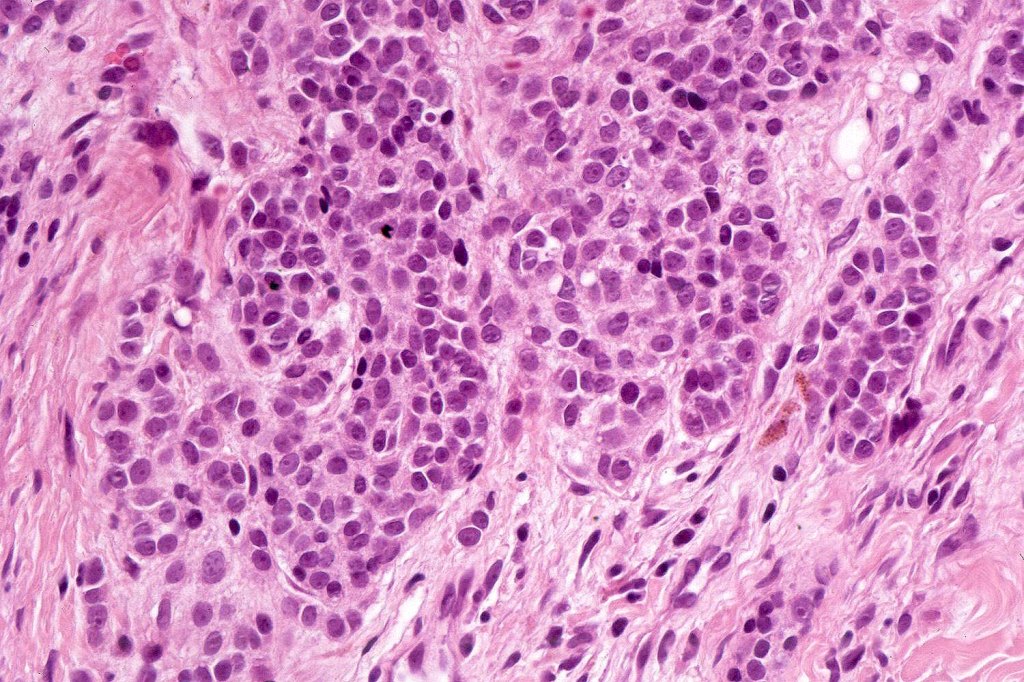

•Verrucous or dome-shaped, at low power, the lesion looks like a nevus

•Expansile nodules or diffuse

•Compression of connective tissue

•Mimics type-A cells, (lesions which mimic type B nevus cells are often classified as small cell melanoma, this is important as the differential diagnosis is very different- see separate blog)

•Subtle or not so subtle impaired maturation with depth (sometimes this is evident at scanning magnification)